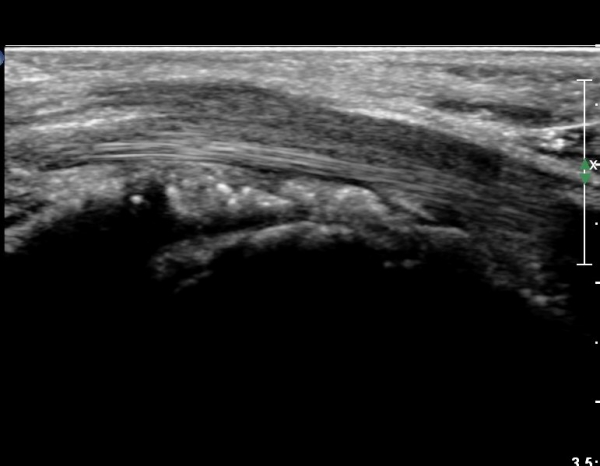

¼ö±Ù°ü Á¾´Ü¸é°Ë»ç¿¡¼ ±¼°î°Ç ½ÉºÎ¿¡ ¼®È¸È¼º À½¿µÀÌ Á¸ÀçÇϰí Àü¹ÝÀûÀÎ ¼öÁö ±¼°î°ÇÀÇ ºñÈÄ, Á¤Á߽ŰæÀÇ ºÎÁ¾°ú

ÈûÁÙ ¹× Á¤Á߽ŰæÀÇ Ç¥ÃþÀ¸·Î ÀüÀ§°¡ °üÂûµÈ´Ù, (»çÁø 5, 6,). ÆÄ¿öµµÇ÷¯°Ë»ç¿¡¼ Ç÷·ùÁõ°¡°¡ °üÂûµÊ´Ù(»çÁø 6).